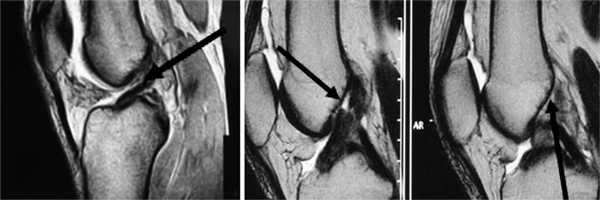

Все пациенты как с хронической патологией коленного сустава, так и с острой его травмой были обследованы с помощью МРТ-диагностики, что резко повысило качество дооперационной диагностики внутрисуставных повреждений коленного сустава. МРТ-диагностику выполняли на томографах 3—4-го поколения, с напряжением магнитного поля свыше 1,5 Tesla, разрешающая способность которых позволяла визуализировать повреждения связочных структур, менисков, суставного хряща, костной ткани коленного сустава (рис. 1 и 2).

Рис. 1. Острое повреждение ПКС коленного сустава. Стрелки указывают на зоны повреждения ПКС.